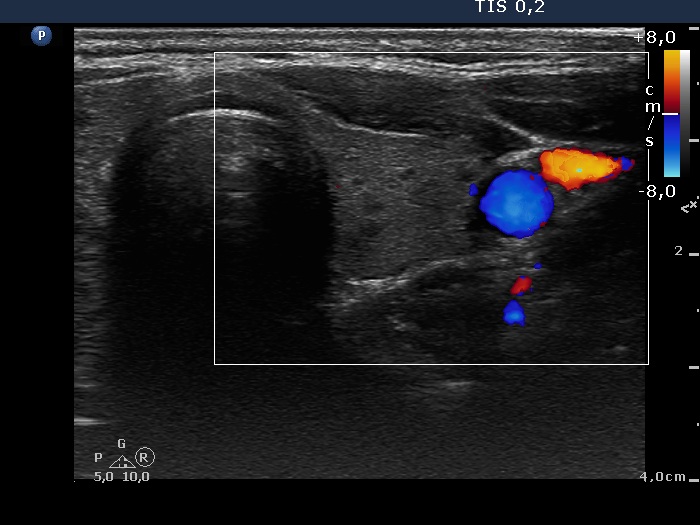

Right lobe, longitudinal scan

Left lobe, transverse scan, color Doppler mode. The vascularization is decreased.